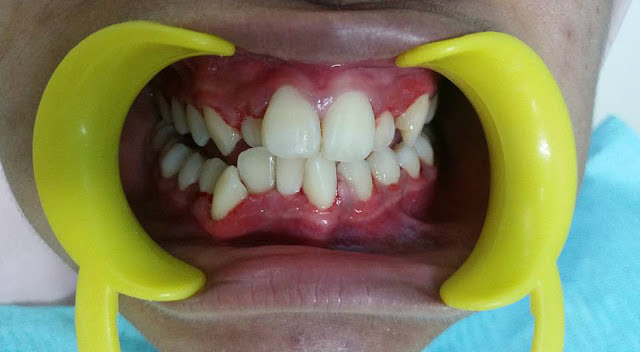

| Gusi bengkak kemerahan, plak gigi tebal, berdarah, berbau, gigi goyang, breket tercabut, gigi berlapis-lapis dan macam-macam lagi masalah berlaku akibat fake braces ini |

Selepas diperiksa, teruknya gusi dia yang bengkak berdarah, berbau, gigi pula bergoyang, ada bracket yang tercabut, sisa makanan tak payah ceritalah.

| Ini selepas doktor cabut fake braces dan scaling, nampak lebih bersih dari sebelumnya |